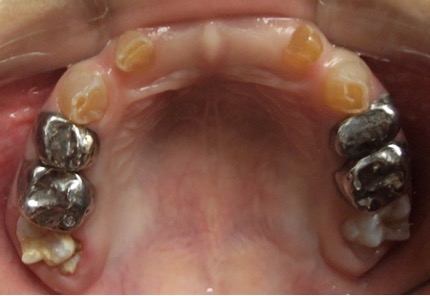

En el año 2010, el mantenedor de espacio fijo superior se descementó, pero debido a la cercana erupción de los incisivos centrales superiores permanentes obser-vada radiográficamente (Figura 5), se decidió no recementarlo, confeccionando coronas de acero independientes en los 4 molares superiores primarios (5.4, 5.5, 6.4 y 6.5) y en el 7.5, previa restauración de las lesiones de caries con ionómero vítreo (Figura 6). Cuando se observó la erupción del 4.1 y 3.1, y de los 4 molares permanentes, se realizaron 3 aplicaciones de barniz de fluoruro de sodio al 5%, cumpliendo con los protocolos establecidos.

Figura 6: Postoperatorias clínicas maxilar superior e inferior año 2010.